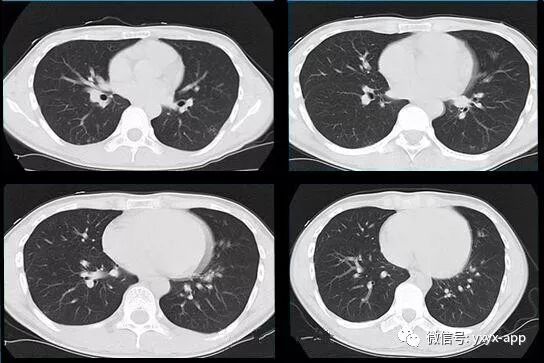

10天后复查

评论:两肺斑片状磨玻璃影,与周围组织分界清楚,呈“地图样”表现,部分病变延伸至胸膜下,部分小叶间隔增厚,气管居中,肺门及纵膈未见肿大淋巴结影,未见胸腔积液。患者青年男性,临床症状轻微影像表现严重,抗炎治疗无效。考虑肺泡蛋白沉积症

CT表现:

1、两肺较淡的斑片状磨玻璃影,不呈叶段分布,病变可延伸至胸膜下,其中磨玻璃影中可见小结节影,磨玻璃影与正常肺组织分界清楚,形成“地图样”改变,这种地图样分布的原因,可能是由于这种斑片影以肺小叶为病变单位,小叶间隔在一定程度上限制了病变的蔓延;

2、由于小叶间隔和小叶内间隔的增厚形成网格状阴影改变,弥漫的磨玻璃影及其内部的网格小叶间隔增厚形成了“铺路石样”改变;

3、实变区具有多样性,多种不同程度的病变共存,病灶内可见支气管气像;

4、病变部位以肺门及双下肺明显。